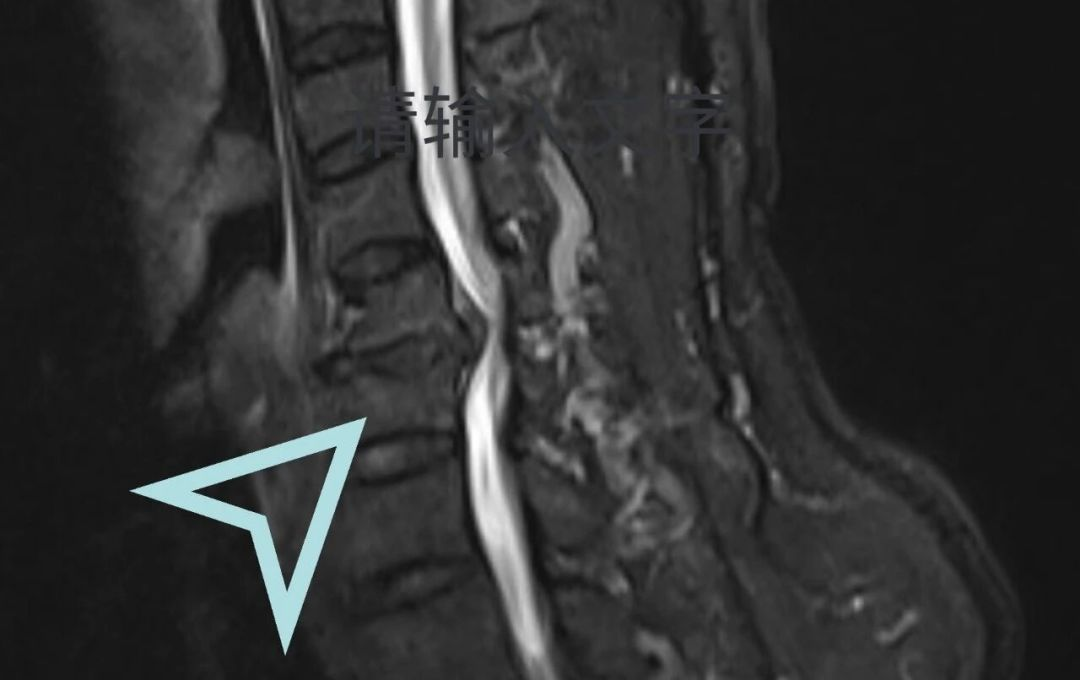

立即安排颈椎MRI检查让病灶“无所遁形”

检查结果实锤!李先生颈椎椎管狭窄、脊髓受压明显,确诊为脊髓型颈椎病——颈椎病里的“狠角色”!

脊髓型颈椎病是颈椎病中最严重的类型之一,是由于颈椎退变导致椎间盘突出、骨赘增生、后纵韧带肥厚等压迫供应脊髓的血管,从而出现颈脊髓损害的颈椎疾病。其主要症状包括四肢麻木、无力,以及大小便功能障碍等。脊髓型颈椎病好发于中老年人,且男性居多,因保守治疗效果差,常需要手术治疗。

其症状多为四肢疼痛、麻木无力,足踩棉花感,走路易跌倒等。病情比较轻的会影响生活及工作,病情严重的可能会出现大小便及性功能障碍,甚至四肢瘫痪。